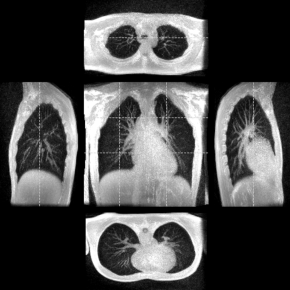

En d’autres termes, cette technique non-invasive permet d’acquérir du signal IRM pendant dix minutes au cours desquelles le volontaire va respirer librement environ une centaine de fois. Les mesures réalisées vont ensuite être rephasées dans un cycle moyen afin de disposer de suffisamment de signal pour établir, au cours du temps, une dynamique pulmonaire représentative en trois dimensions. « Cette approche permet de bien faire ressortir le système vasculaire alimentant le poumon. Celui-ci définit des marqueurs solides que nous utilisons pour caractériser les déformations du poumon au cours de ce cycle respiratoire moyen », ajoute le chercheur de BioMaps.

De cette dynamique respiratoire 3D, il est possible de déduire la variation de volume au cours du temps et extraire les courbes débit/volume au cours du cycle respiratoire en chaque point du poumon, là où la spirométrie standard permet d’avoir cette donnée seulement au niveau de la bouche. Autrement dit, sur une respiration libre, un million de mesures régionales sont réalisées pour un volume courant de l’ordre de 0,5 µL au lieu d’une seule mesure globale qui serait faite au niveau de la bouche pour un volume courant de 0,5 L.